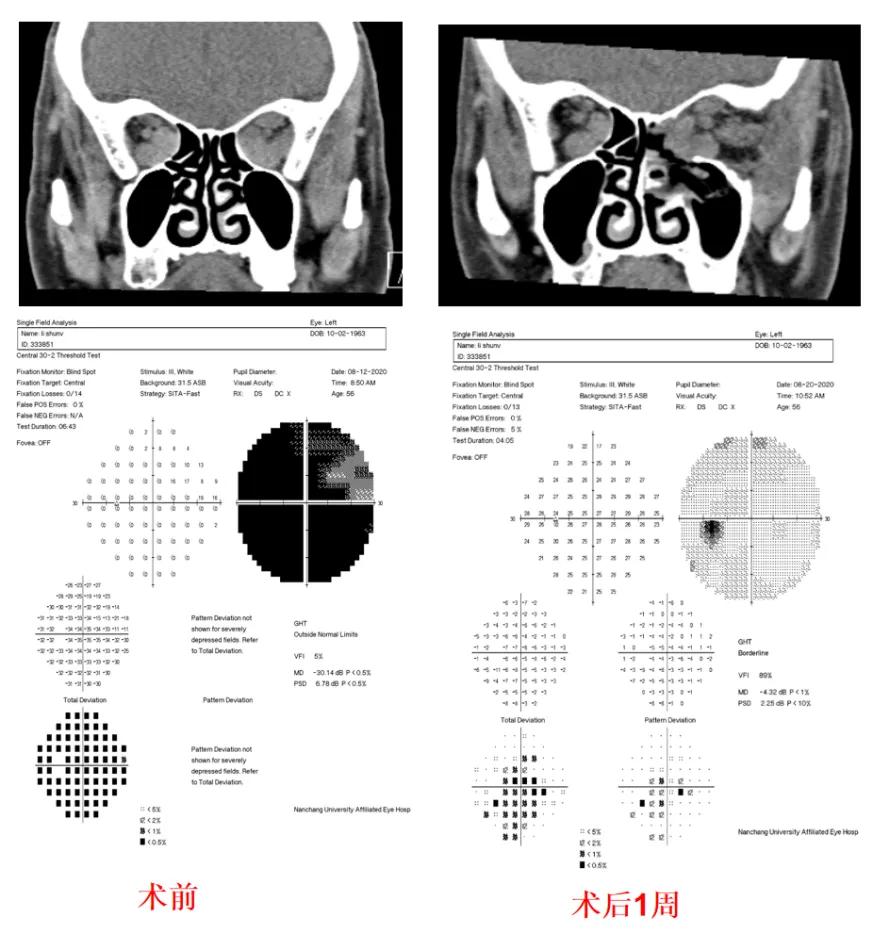

患者女性,56岁,主诉双眼球突出1年,左眼视力下降3个月。

专科检查:

视力:右眼1.0,左眼指数/30cm;眼球突出度:20mm>--102mm--<21mm。诊断:1.左眼压迫性视神经病变(DON)2.双眼甲状腺眼病(右眼中重度,左眼极重度)。

手术方案:内镜下经鼻入路眶内侧壁减压+数字医学手术导板辅助下外侧眶减压术。

术后1周专科检查:

视力:右眼1.0 左眼1.0;眼球突出度:20mm>--102mm--<15mm;眼球各个方向运动可,无视物重影。

图3.患者术前与术后1周眼眶冠状位CT及视野检测结果。